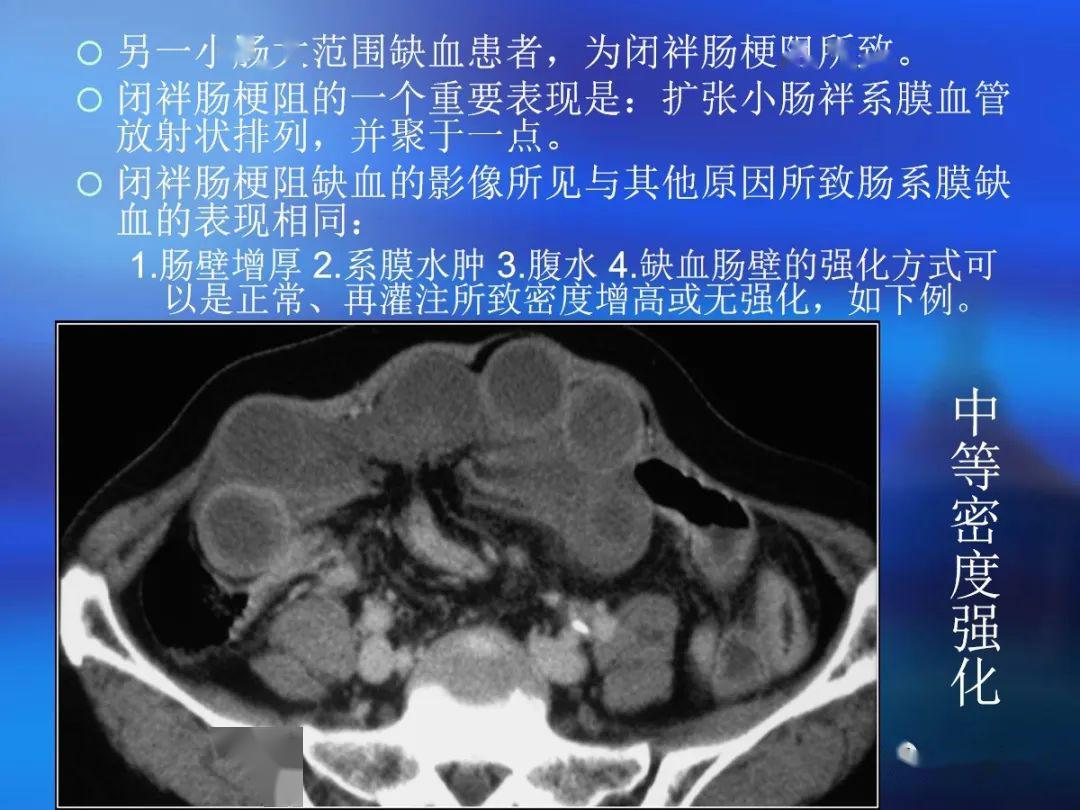

脂肪有时见于乳糜泻ct 评价肠壁增厚存在的问题肠道是蠕动的空腔器官